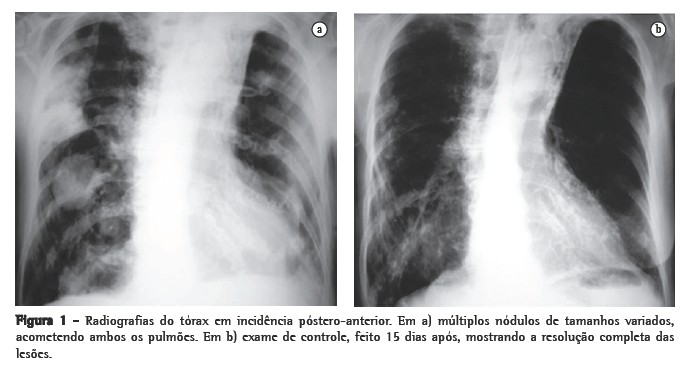

Foi realizada tomografia computadorizada (TC) do tórax, que confirmou a presença dos nódulos com tamanhos variados, sendo alguns escavados (Figura 2). Três amostras seguidas de escarro com pesquisa de bacilos álcool-ácido resistentes e fungos (coloração pela prata) foram negativas. A bacterioscopia (Gram) mostrou a presença de bactérias filamentosas nas três amostras colhidas de escarro, fortemente sugestivas de Nocardia spp., confirmada pela coloração de Ziehl- Neelsen, mostrando a característica resistência parcial à solução álcool-ácido (Figura 3).

Nódulos, massas escavadas, derrame pleural, pneumotórax, opacidades em vidro fosco e padrões intersticiais podem também ocorrer.(1,4,5,11) Alguns estudos mostram que, em pacientes HIV positivos, existe um percentual maior de lesões escavadas.(8) A consolidação alveolar nos lobos superiores é muitas vezes confundida com tuberculose pulmonar.(6) Embora as alterações vistas na TC sejam ­semelhantes às das radiografias convencionais, a TC é superior na demonstração da exata localização e extensão das lesões, assim como na diferenciação entre lesões pulmonares e pleurais.(5) No caso relatado, a paciente apresentava imagens nodulares de tamanhos variados, disseminadas por ambos os pulmões, e algumas delas escavadas.